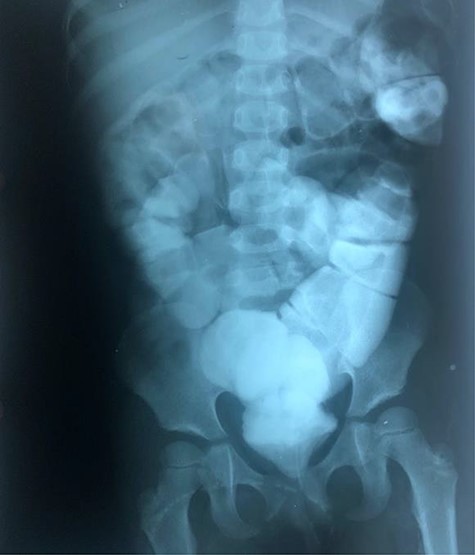

The clinical case consisted of a 4-year-old female patient who presented with long-standing constipation, which afflicted her since birth. The mother referred that the patient could only defecate 2 to 3 times per week, requiring the administration of rectal enemas, lactulose and plum juice. Upon physical examination, the patient presented increased frequency of intestinal sounds, no abdominal tenderness on palpation, tympanic sound to percussion, abdominal distention and a positive blast sign. A water-soluble contrast enema was performed to evaluate the colonic segments and rectum. The study displayed a distal narrow segment with proximal distention representing the pathognomonic transitional zone (Figs 1 and 2). Rectal biopsies were taken at 3, 5 and 10 cm from the anal margin. The biopsy at 3 cm showed hyperplasia of the muscularis mucosae and absence of the submucosal and myenteric nerve plexuses. However, the other two segments that were taken showed no abnormal findings. According to these findings, the patient was diagnosed with USHD. Treatment consisted of transanal myectomy of the internal anal sphincter.

Radiographic abdominal lateral view of water-soluble contrast enema.